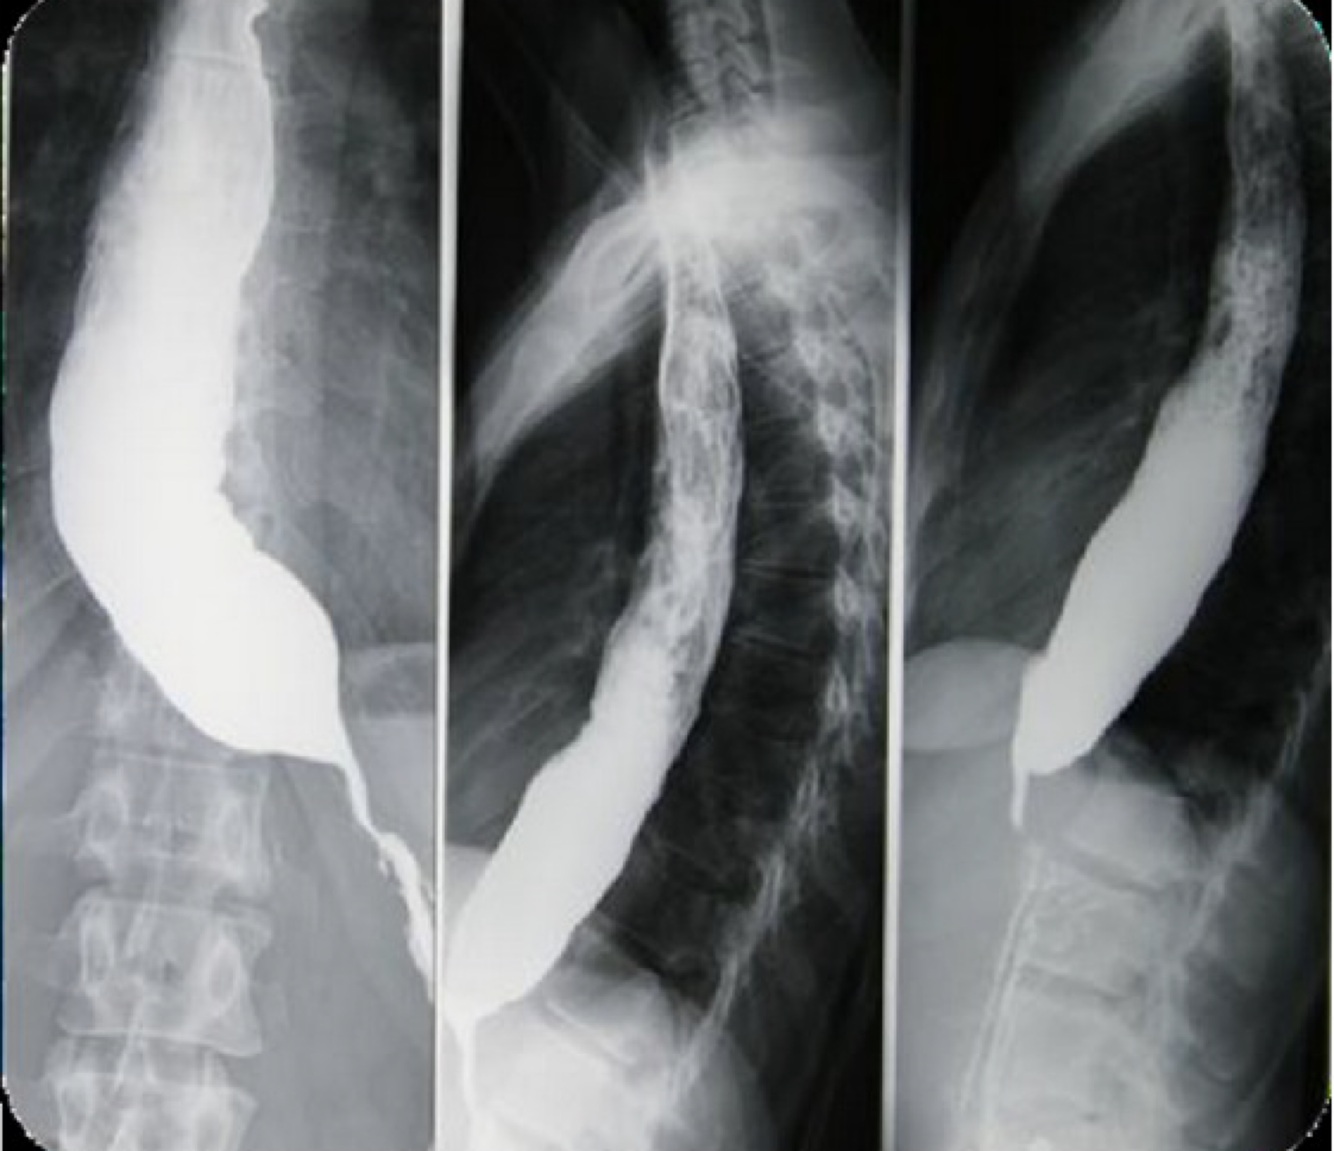

esophageal cancer at the gastroesophageal junction